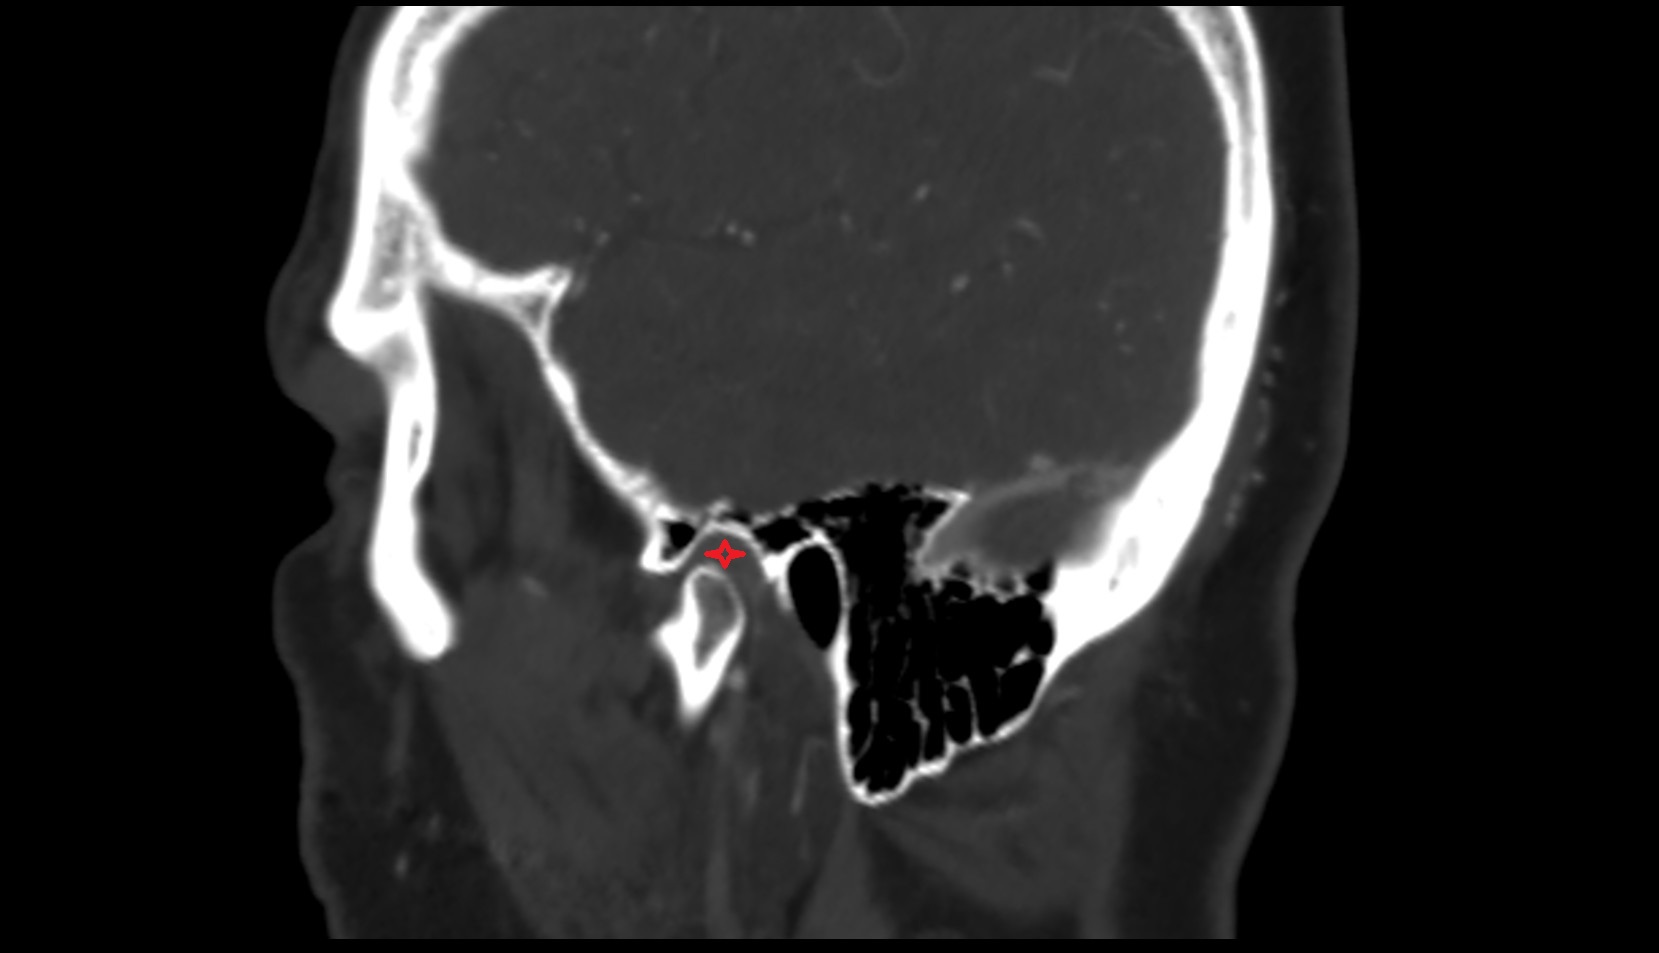

- Temporomandibular joint

- Mandibular condyle

- Mandibular fossa

- Articular eminence

- Articular disc of temporomandibular joint